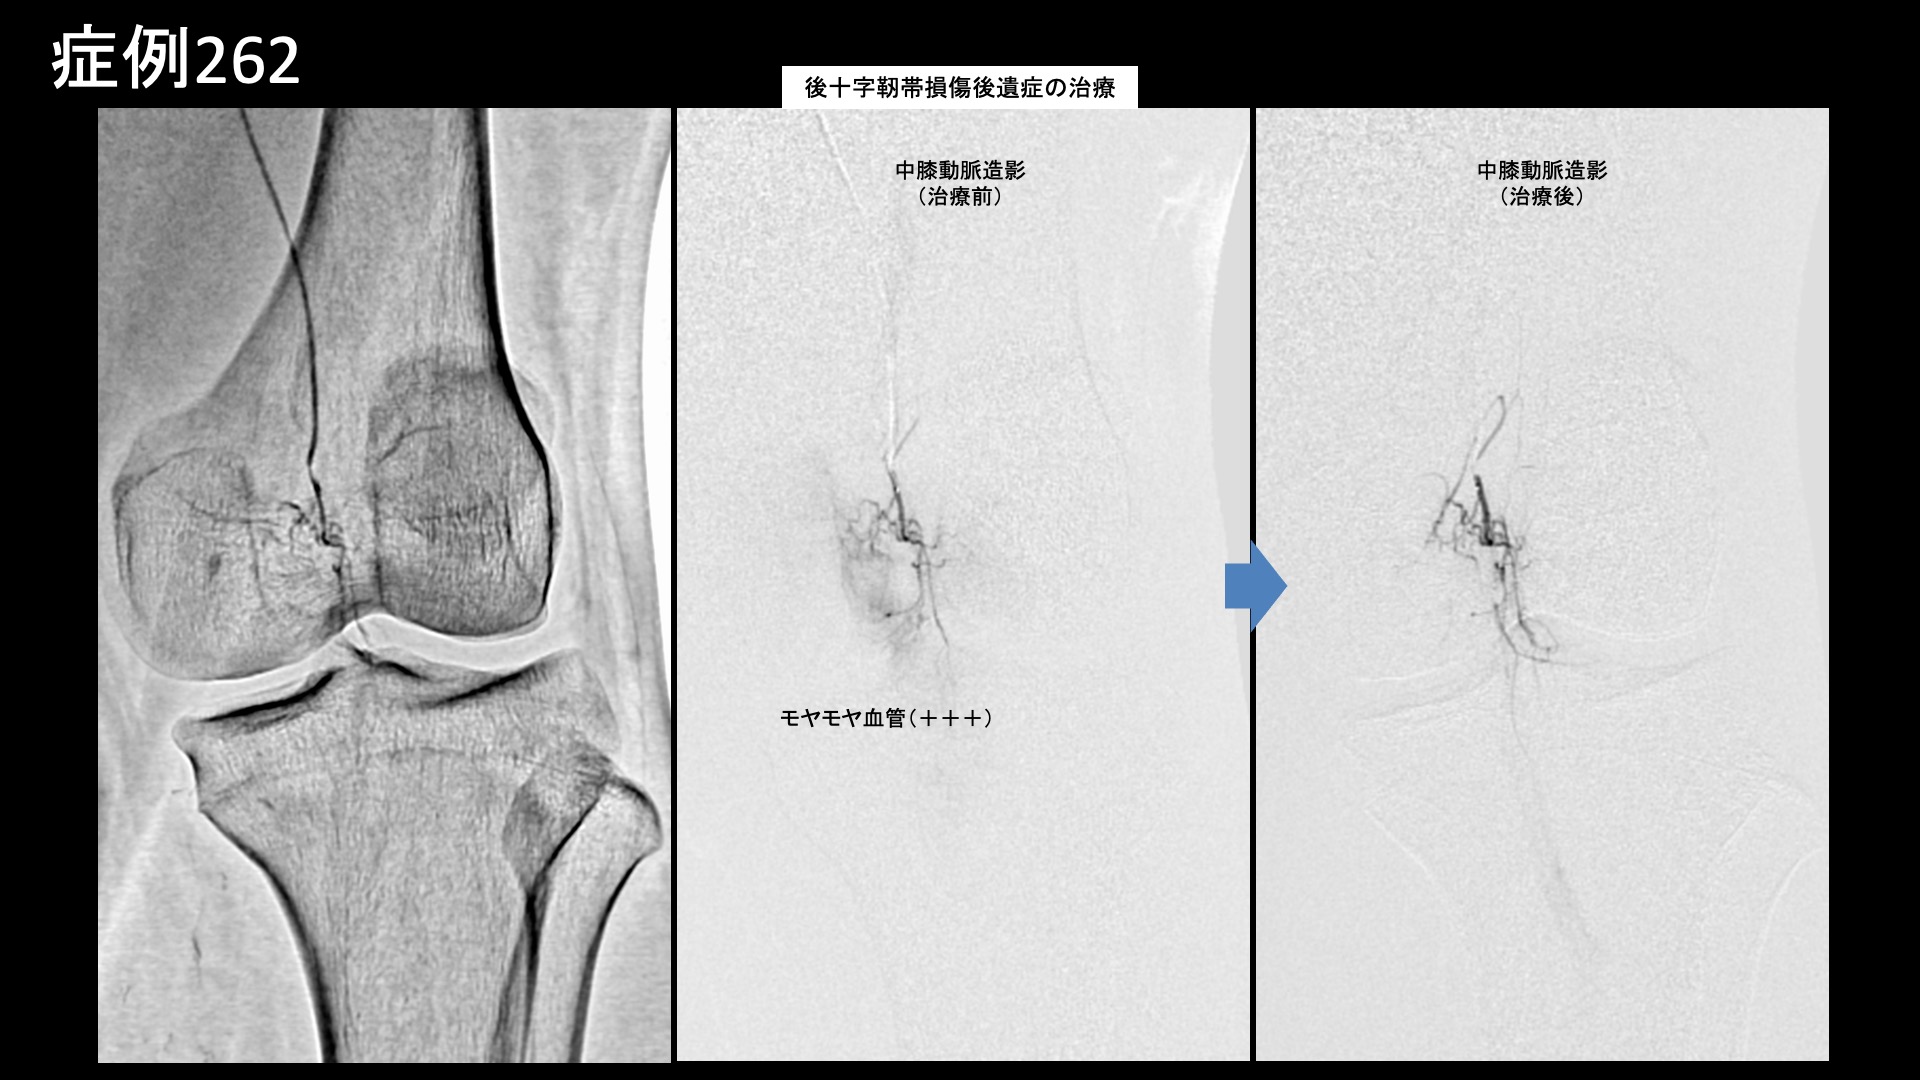

膝:変形性膝関節症など 【20代:男性】パフォーマンス向上のため、スケートボード選手が決断した後縦靭帯損傷後遺症に対するモヤモヤ血管治療(スケートボード、後縦靭帯損傷、外傷後遺症) 2026.02.13 鴨井院長による動画解説 受診までの経過 スケートボード選手です。1年半前から左膝の裏側の痛みがありました。左膝を立てると痛み、ぐっと曲げた時も痛みが増すが、正座までしてしまえば痛くありませんでした。MRI検査の結果、後縦靭帯損傷と診断され、保存的治療の方針となりました。日常生活や軽めの練習では問題ないものの、しっかり曲げられないと競技パフォーマンスを発揮できないことから、治療を決断し当院を受診されました。 診察時の所見 MRI検査にて上記のように確定診断後です。慢性痛に移行しており、モヤモヤ血管の治療適応と判断し、モヤモヤ血管(病的新生血管)に対する運動器カテーテル治療(微細動脈塞栓術)を受けていただきました。 治療の所見 血管造影を行うと、後縦靭帯の血行を担っている中膝動脈に一致して、モヤモヤ血管が濃染像として描出されました。前脛骨反回動脈においても同様にモヤモヤ血管が認められました。特徴的でありご本人に確認したところ、よく打撲する部位とのことでした。繰り返しの打撲により形成されたものと思われました。治療後、これらのモヤモヤ血管は画像上速やかに消失しました。尚、再現痛も一致していました。その他複数箇所の治療を行い終了しました。 *再現痛とは、薬液投与時に普段の痛みが一定程度再現される現象です。責任血管の同定のための参考とします。 治療前画像:損傷を受ける、あるいは繰り返しのストレスにより発生した異常な新生血管 治療後画像:カテーテルを用いて塞栓物質を血管内に投与し新生血管を塞いだ状態 治療費用:治療する部位によって費用が異なりますのでこちらをご参照ください。 主なリスク・副作用等:針を刺した場所が出血により腫れや痛みを生じたり、感染したりすることがあります(穿刺部合併症)。造影剤によるアレルギー(皮膚のかゆみ・赤み・息苦しくなるなどの症状)が出ることがあります。 治療後の経過 治療後2週間、数値で表すのは難しいが、いつも気になっていた部位の痛みが軽減され、問題なく競技ができているとのことでした。治療後1ヶ月半、ぐっと曲げた時に痛むことがなくなりました。転倒した時に気になる痛みもあったのですが、それもあまり痛まなくなりました。十分な練習ができるようになり、パフォーマンスも良好とのことでした。治療後3ヶ月、転倒時の痛みも無くなり、すこぶる調子が良いとご報告いただきました。経過良好であり終診としています。 スポーツ選手の場合、日常生活では困っていないが、競技パフォーマンスに支障をきたす痛みであるということが少なくありませんが、まさにそうした症例であり、パフォーマンスの向上に奏効しました。外傷後の後遺症はモヤモヤ血管治療の良い適応です。中々他に手立てがなくお困りの方も多いと思いますので、ご参考にしていただければと思います。 【60代:女性】発症2ヶ月の帯状疱疹後神経痛(鳩尾~乳房下~背中の痛み)に対するモヤモヤ血管治療(帯状疱疹後神経痛) 前の記事 【50代:女性】顔面に生じた難治の痺れと痛み、顔面骨折に三叉神経第2枝損傷を合併した外傷後疼痛に対するモヤモヤ血管治療(外傷後疼痛、顔面骨折、三叉神経第2枝損傷) 次の記事